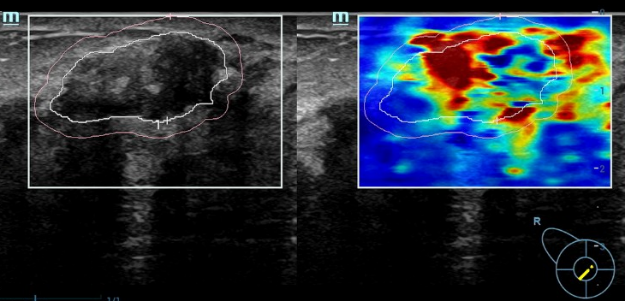

刘女士听从了我的建议,重新做了加入了超声弹性成像技术的彩超。结果确实令人担心:右乳肿物:BI-RADS 4b类(中度可疑恶性);左乳肿物:BI-RADS 4a类(低度可疑恶性);右侧腋窝淋巴结异常肿大。尽管钼靶报告提示“BI-RADS 3类”,刘女士提出质疑:“钼靶不是说没事嘛?”,我仍旧坚定的建议她:“必须穿刺!

右侧乳腺彩超+弹性成像(BI-RADS 4b类)